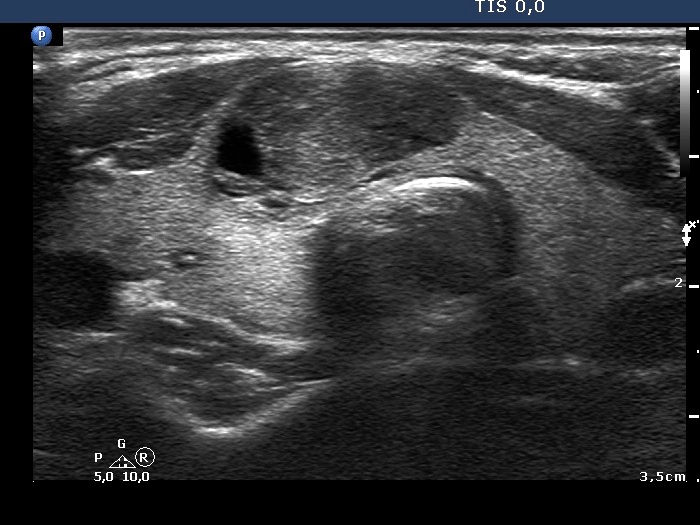

One year after the first examination (second row of images):

Clinical presentation. The patient had no complaints.

Palpation: unchanged.

Hormonal evaluation: TSH 0.91 mIU/L.

Ultrasonography. The cystic areas of the nodule in the isthmus have increased. The lesion presented more bright echogenic lines and granules which corresponded to figures caused by posterior back wall enhancement.